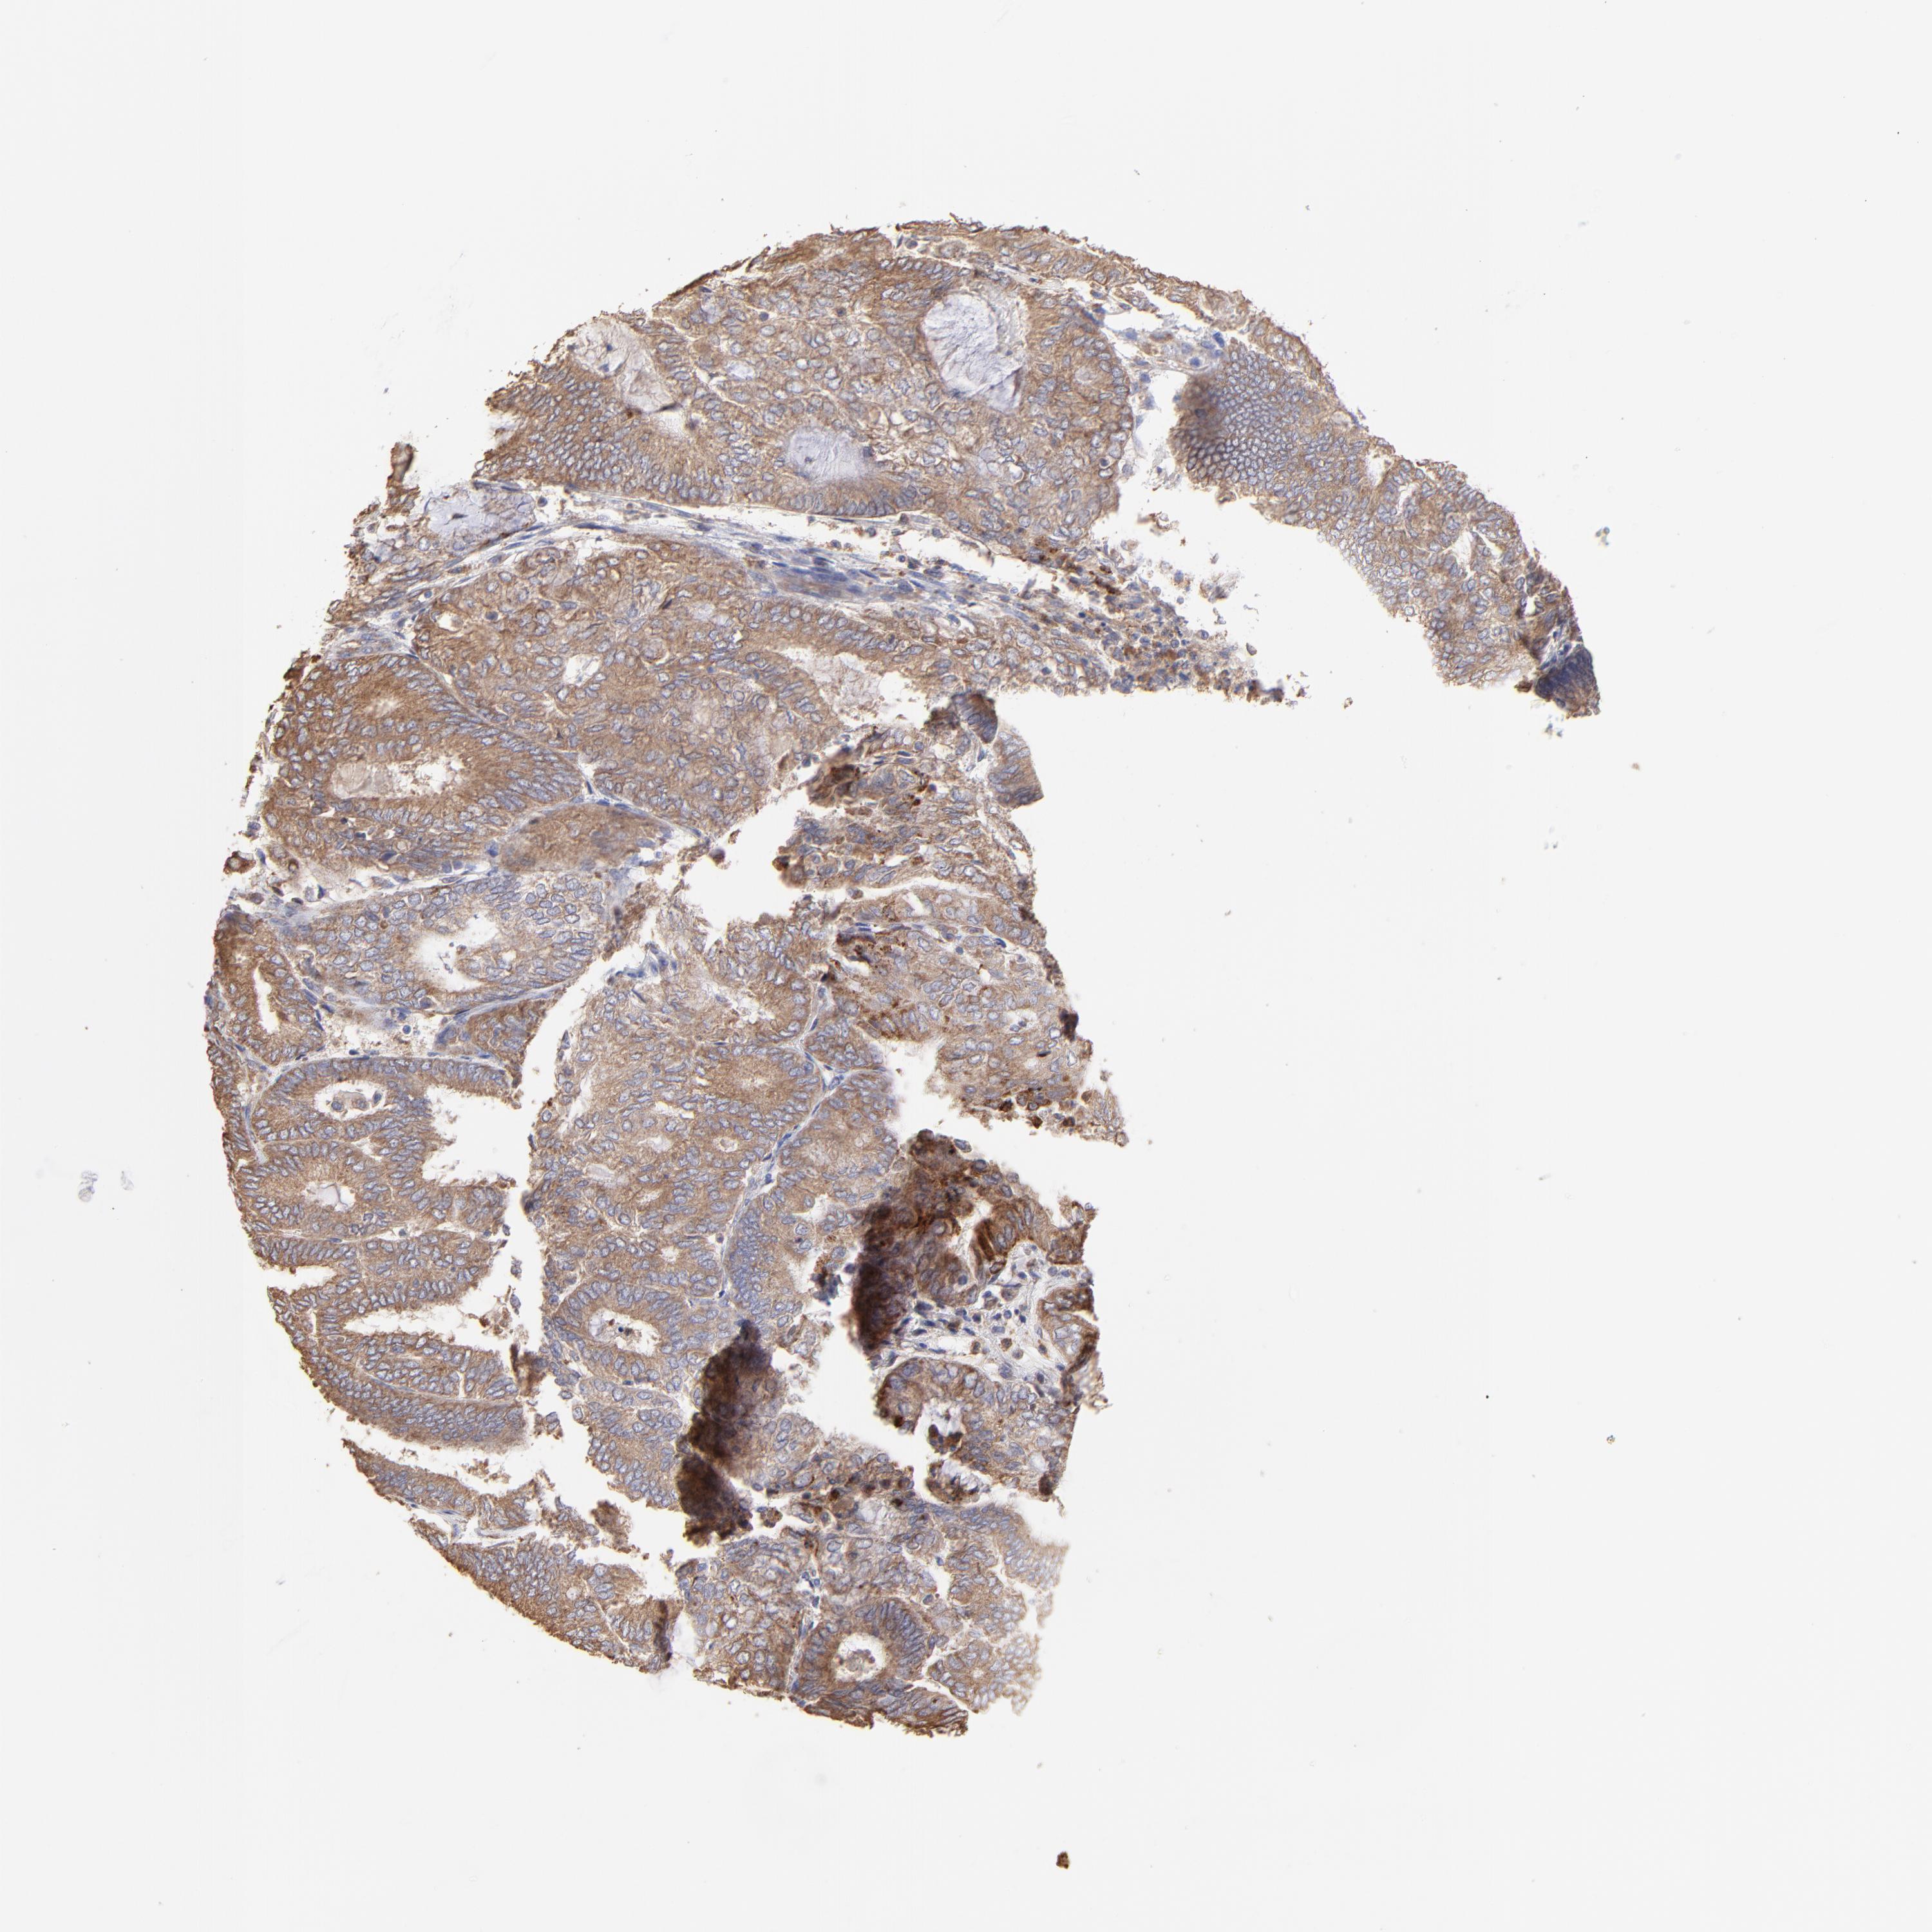

ENDOMETRIAL CANCER - Protein expressioni

A mouse-over function shows sample information and annotation data. Click on an image to view it in a full screen mode. Samples can be filtered based on level of antibody staining by selecting one or several of the following categories: high, medium, low and not detected. The assay and annotation is described here.

Note that samples used for immunohistochemistry by the Human Protein Atlas do not correspond to samples in the TCGA dataset.

Antibody stainingi

Antibody staining in the annotated cell types in the current human tissue is reported as not detected, low, medium, or high, based on conventional immunohistochemistry profiling in selected tissues. This score is based on the combination of the staining intensity and fraction of stained cells.

Each image is clickable and will lead to virtual microscopy that enables deeper exploration of all samples and also displays staining intensity scores, fraction scores and subcellular localization as well as patient and tissue information for each sample.

Antibody HPA002117

Staining

High

Medium

Low

Not detected

Intensity

Strong

Moderate

Weak

Negative

Quantity

>75%

75%-25%

<25%

None

Location

Nuclear

Cytoplasmic/membranous

Cytoplasmic/membranous,nuclear

Adenocarcinoma, NOS